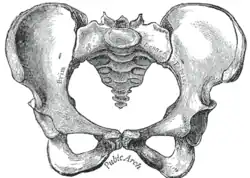

| Comparação entre uma pelve androide (esquerda) e uma ginecoide (direita). | |

A obstetrícia tradicional caracterizou quatro tipos de pelves:

- Ginecoide: forma ideal, com abertura superior arredondada a levemente oval (entrada obstétrica ligeiramente menos transversa).

- Androide: abertura triangular, espinhas isquiáticas proeminentes, arco púbico mais angulado.

- Antropoide: o maior diâmetro transverso é menor que o diâmetro obstétrico ântero-posterior.

- Platilipeloide: abertura superior achatada, com diâmetro obstétrico reduzido.